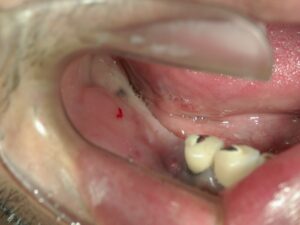

↑歯がない状態です。以前はブリッジをしていたようですが、歯の喪失によりインプラント治療が必要です。